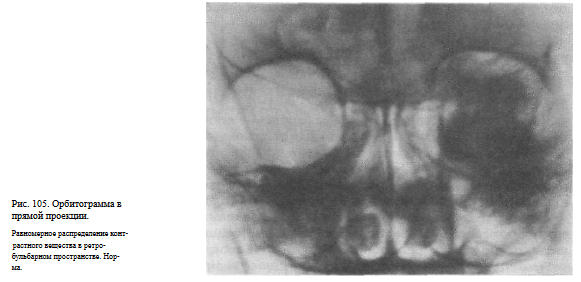

ОРБИТОГРАФИЯ

Назначение исследования — выявление объемного процесса в орбите путем контрастирования заглазничного пространства.

Методика исследования. Под местной анестезией вводят иглу через нижнее веко параллельно нижней стенке глазницы на глубину 1,5—2 см, и через нее вливают в теноново пространство 2—3 мл 0,5 % раствора новокаина, а затем 4—5 мл 20 % раствора гипака. Рентгенограммы выполняют через 1 и 10 мин после введения контрастного вещества в прямой (задней) и боковой проекциях.

Информативность исследования. Контрастное вещество равномерно распределяется в жировой клетчатке заглазничного пространства и на снимках в норме имеет типичную конфигурацию: на прямом снимке — форму прямоугольника с закругленными краями и округлым дефектом наполнения в центре в месте прохождения зрительного нерва (рис. 105), а на боковом снимке — конусовидную форму с полусферическим вдавлением в области основания, соответственно заднему полюсу глазного яблока.

При опухолях или других объемных процессах распределение контрастногоещества неравномерное, с наличием дефектов наполнения (рис. 106).